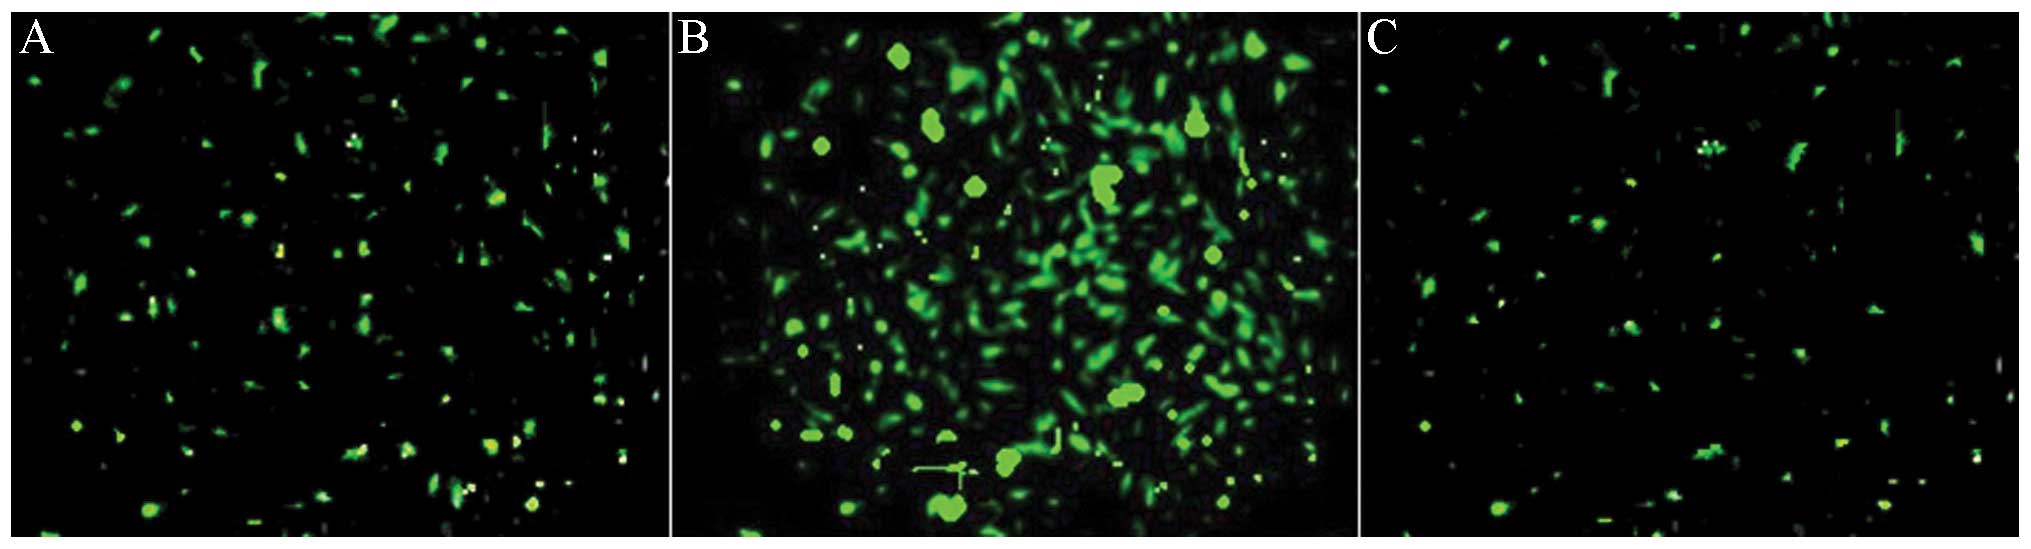

Efficient transfection of lentivirus

Previous studies have shown that local virus delivery to precollar-induced abdominal aortic atherosclerosis of pigs has resulted in efficient transfection to abdominal aortic atherosclerosis (24). GFP expression provides an efficient and convenient method by which to check lentiviral transfection efficiency. Therefore, GFP was analyzed in the abdominal aortic atherosclerosis 1 week after transfection (Fig. 3A). siRNA transfection (indicated by strong green fluorescence) was observed most significantly after 2 weeks after transfection (Fig. 3B). When the study was terminated, GFP remained weakly visible, two months after transfection (Fig. 3C). These results demonstrated the efficiency of the in vivo transfection of siRNA lentiviruses in the abdominal aortic atherosclerosis. Local transfection of the virus did not affect the normal functioning of the animals and did not result in weight change (34.89+4.16 kg in transfected pigs vs. 34.54+3.87 kg in mock-siRNA and 31.96±4.84 kg in saline).

Figure 3

Detection of green fluorescence protein in aortic atherosclerosis of pigs in Cx-37 siRNA group (magnification, ×200). (A) One week; (B) two weeks; (C) two months after transfection.